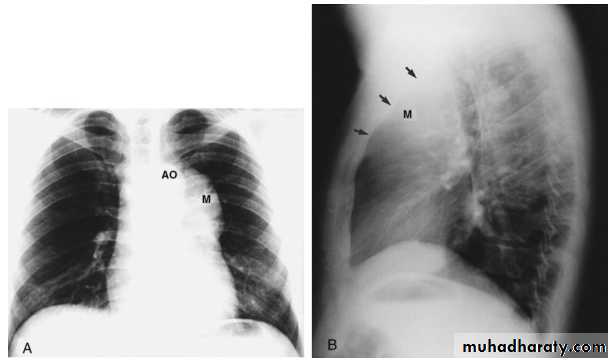

Thymoma.

A chest x-ray (A) reveals an unusual contour over the left hilum (arrows). That the hilum is not obscured (no silhouette sign) indicates that the mass must either be in front of or behind the hilum. A computed tomography scan (B) reveals a soft tissue mass (arrow) just to the left of the aorta. This is the most common location of a thymoma.